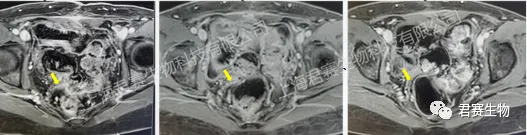

受试者接受TIL回输前、回输后6周及回输后12周影像资料

出院后,每次随访结果都带来惊喜:肿瘤标志物持续降低,肿瘤不断缩小,治疗后两个多月,各项检查指标均恢复正常。如今,4年过去,L女士早已回归正常生活和工作,无需长期服药,也不用再频繁辗转于各大医院,彻底摆脱了癌症带来的生理和心理煎熬。